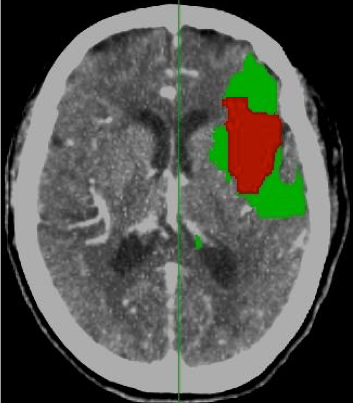

Lo que hemos visto antes es un análisis cuantitativo. A pesar de todo, en la urgencia puede ser incluso más util el análisis visual o cualitativo. Las casas comerciales han desarrollado incluso mapas resumen que muestren ese «mismatch» o discordancia de forma gráfica.

Se pintan unos mapas que muestran:

- Rojo = zona infartada. El volumen es menor de 2 litros.

- Verde = zona isquémica salvable (TTM – CBV). TTM mayor del 145% y volumen mayor de 2 litros.